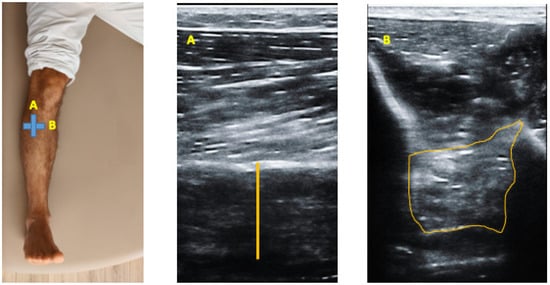

2.3. Ultrasonography Examination

2.4. Image Analysis